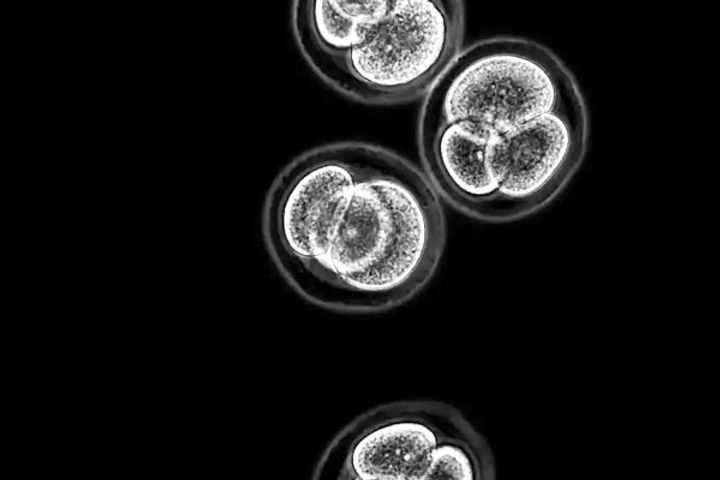

Researchers in Jerusalem have discovered a process to transform skin cells into the three significant stem cell types which develop early-stage embryos. The work, done in mouse cells, has massive implications in modeling embryonic disease and placental dysfunctions. It can also pave the way to develop whole embryos from skin cells. These reprogrammed skin cells have been named Induced Plutipotent Stem Cells.